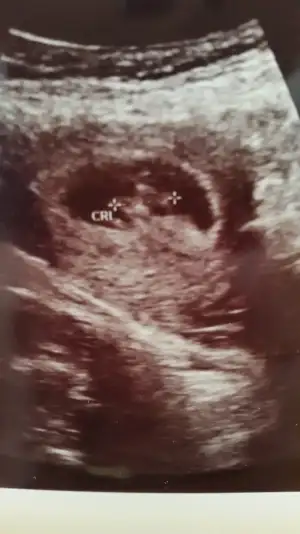

Kaç haftalik canım maşallah bebeğine

Aslinda suan 7+6 oldum ama doktora gittigimde 6+5ti canim kalp atisini duyduk o gun 2 gun geriden gelyodu snada masaallahh canim 9 haftalik olmussun heraldeKaç haftalik canım maşallah bebeğine

Sağlıklı büyüsünlerde geriden gelsede farketmez canim 8+4 ümAslinda suan 7+6 oldum ama doktora gittigimde 6+5ti canim kalp atisini duyduk o gun 2 gun geriden gelyodu snada masaallahh canim 9 haftalik olmussun heralde